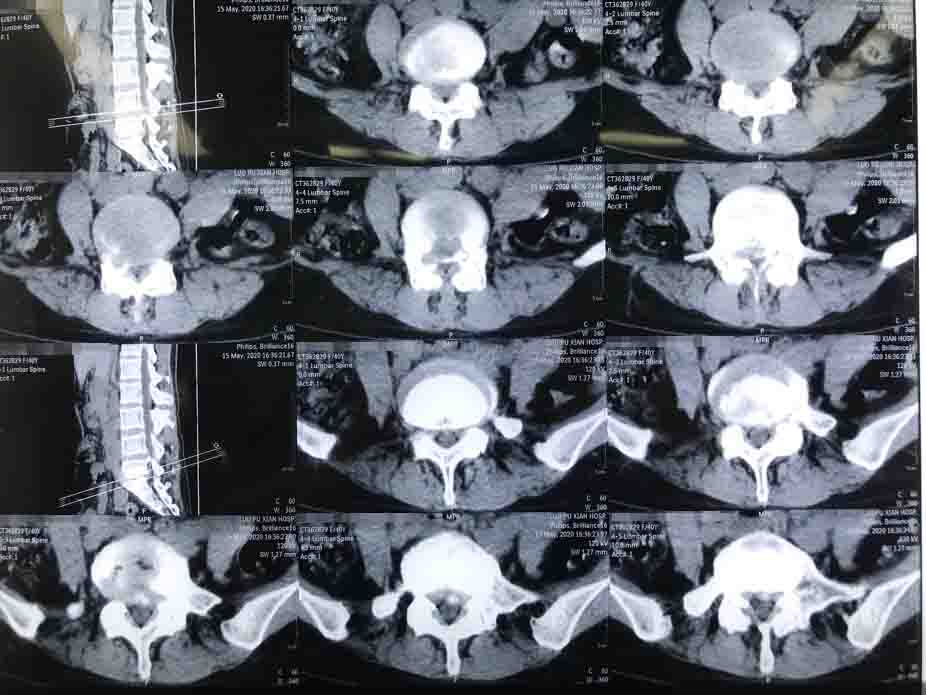

1,患者影像資料.jpg

患者是一名30多歲的維族女性,腰痛伴雙下肢疼痛,間歇性跛行。由于癥狀較重,生活質(zhì)量已明顯下降,反復發(fā)作,經(jīng)保守治療無效,需要盡快給予手術(shù)治療。

我和同事在詳細查體和閱片后,明確了患者責任節(jié)段為腰4/5,再對脊柱穩(wěn)定性進行評估,最終制定了”腰4-5后路全椎板減壓、髓核摘除、神經(jīng)根松解、椎弓根釘棒系統(tǒng)內(nèi)固定術(shù)”的手術(shù)方案。